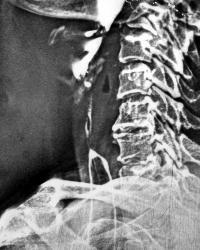

Вероятно перфорация,заглоточный абсцесс.

Да, можно предположить(газ в мягких тканях кпереди от позвоночника, на уровне гортани).

Уровень жидкости в превертебральном пространстве, угроза медиастинита. Контраст туда не попал, вероятно, отеком закрыто раневой канал. Рекомендована КТ для уточнения положения и распространения процесса. Если КТ нет, линейная томография стоя(сидя)

Перфорация стенки глотки, газовый заглоточный абсцесс, вскрытие и дренирование, благополучный исход без медиастинита...

Скелетотопия пищевода, глотка переходит в пищевод на уровне 6-7 шейного позвонка.